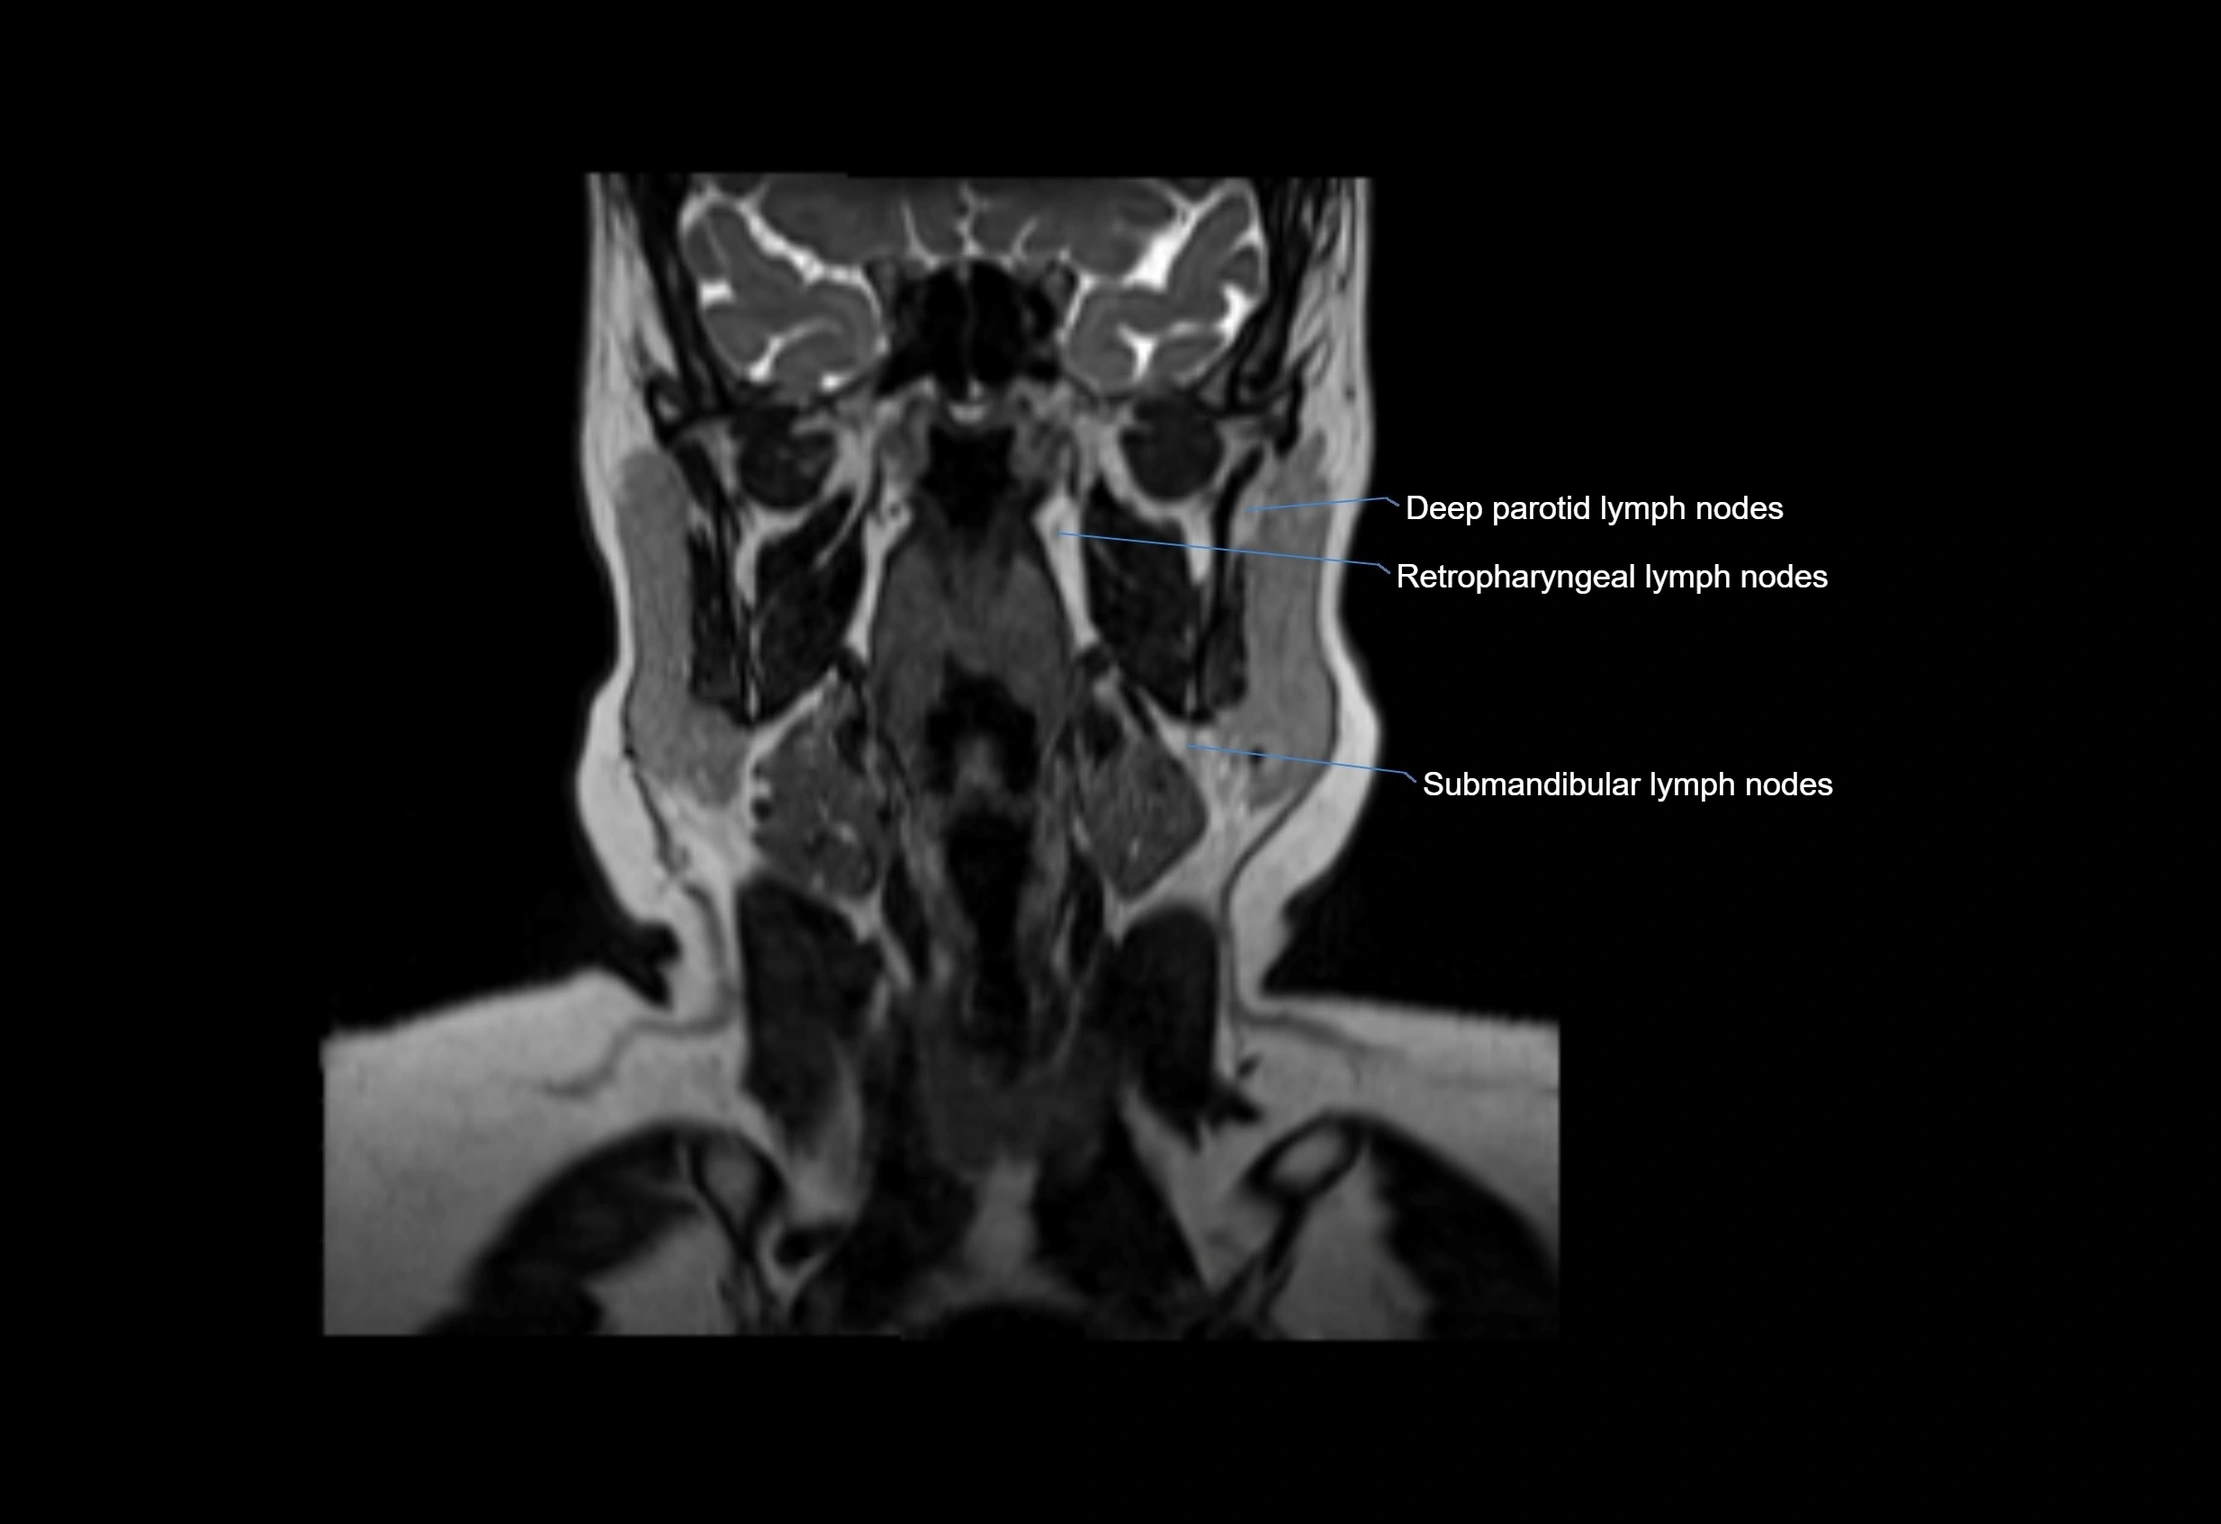

Accessory lymph nodes

Accessory lymph nodes are small, secondary lymph nodes located along the main facial and cervical lymphatic chains, often adjacent to primary lymph nodes, such as preauricular, submandibular, or occipital nodes. They are typically less than 5 mm in diameter, embedded within subcutaneous fat or connective tissue, and may be variable in number and location. These nodes provide additional filtration and immune surveillance for lymph collected from the face, scalp, and neck regions. Accessory lymph nodes are usually non-palpable in healthy individuals but may enlarge in response to infection, inflammation, or metastasis, making them clinically significant.

Location

• Found along primary lymph node chains, including preauricular, submandibular, parotid, and occipital regions

• Embedded in subcutaneous fat or superficial fascia, often lateral or posterior to primary nodes

MRI Appearance

T2-weighted images:

• Nodes show intermediate signal, with surrounding fat bright

• Useful for detecting edema, inflammation, or infiltration

• Fatty hilum may appear slightly hyperintense relative to cortex